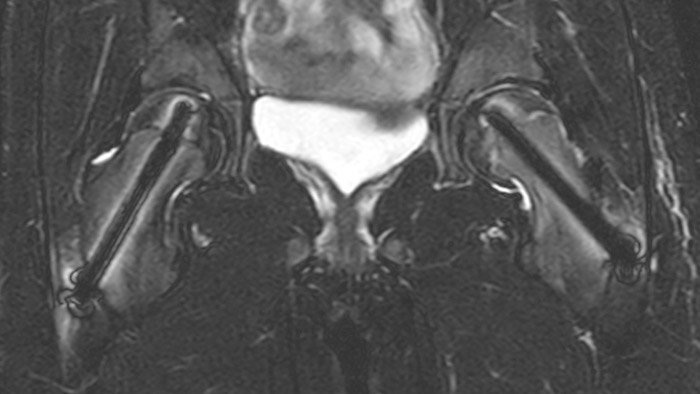

Dural sinus malformation (DSM) Initial examination

After three times of coiling and acryl based embolization

After intervention with two cannulated titan screws, it is important to check that the circumference is normal and without necrosis. The screws can cause major metal artifacts, but O-MAR allows to improve visualization of tissue and bone in the near vicinity of MR Conditional orthopedic implants1. 1 Only for use with MR Safe or MR Conditional implants by strictly following the Instructions for Use